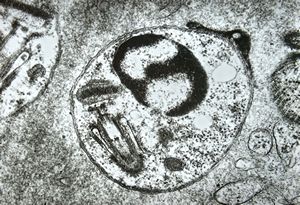

M,10y. | herpes virus - herpetic encephalitis